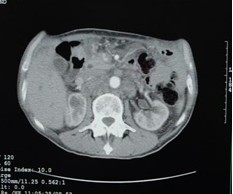

男,60歲,晚期胃癌,腹腔轉(zhuǎn)移,鎖骨上淋巴結(jié)轉(zhuǎn)移,肝,腹腔轉(zhuǎn)移。初治(手術(shù))。治療前CEA 12.95 ng/ml,左鎖骨上轉(zhuǎn)移淋巴結(jié)2.0cm。今又生經(jīng)靜脈滴注,1×1012VP/支/次,3次/周,共30支,聯(lián)合草酸鉑+CF+5-FU化療,2周期。治療后:CEA下降到9.71 ng/ml,左鎖骨上轉(zhuǎn)移淋巴結(jié)縮小到0.5 cm。KPS評(píng)分增加20分,療效評(píng)價(jià)為腫瘤部分消退(PR)。

治療前

治療后